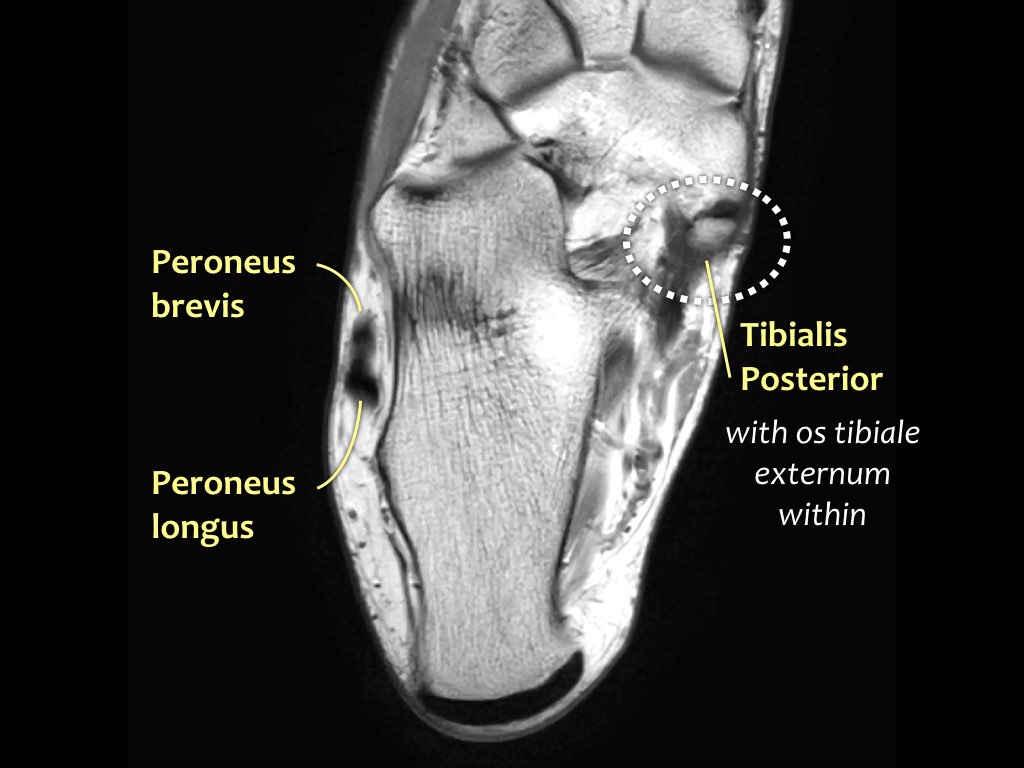

- Khoang ngoài

- Gân cơ mác dài (Peroneus Longus)

- Gân cơ mác ngắn (Peroneus Brevis)

Gân cơ chày sau

Gân cơ chày sau là gân bị tổn thương thường gặp nhất.

Bệnh lý gân biểu hiện bằng tình trạng sưng to bất thường của gân, tuy nhiên cần lưu ý rằng gân chày sau bình thường có thể có kích thước gấp đôi gân cơ gấp các ngón chân dài.

Rối loạn chức năng gân chày sau thường gặp hơn ở phụ nữ và những người trên 40 tuổi.

Tình trạng này gây ra đau và sưng ở mặt trong cổ chân, cùng với biến dạng bàn chân bẹt mắc phải.

Tổn thương gân chày sau ở bệnh nhân trẻ tuổi chủ yếu do chấn thương hoặc sử dụng quá mức.

Khi gân chày sau bị tổn thương, cần kiểm tra kỹ dây chằng lò xo (spring ligament), vì cả hai cùng nhau duy trì vòm bàn chân ở phía trong.

Trong biến dạng bàn chân bẹt, cả gân và dây chằng lò xo đều có thể bị tổn thương.

Các hình ảnh cho thấy bệnh lý gân chày sau (PTT), đồng thời có tổn thương dây chằng lò xo kèm theo.